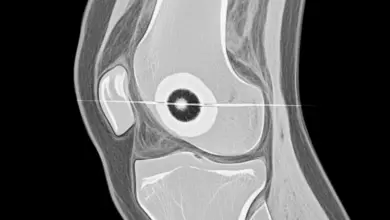

Entre os exames, radiografias podem mostrar alterações ósseas e sinais indiretos, mas a ressonância magnética geralmente é a principal para avaliar cartilagem, osso subcondral, edema ósseo e corpos livres.

Em casos selecionados, a tomografia auxilia no planejamento, principalmente quando se suspeita de fragmentos osteocondrais.